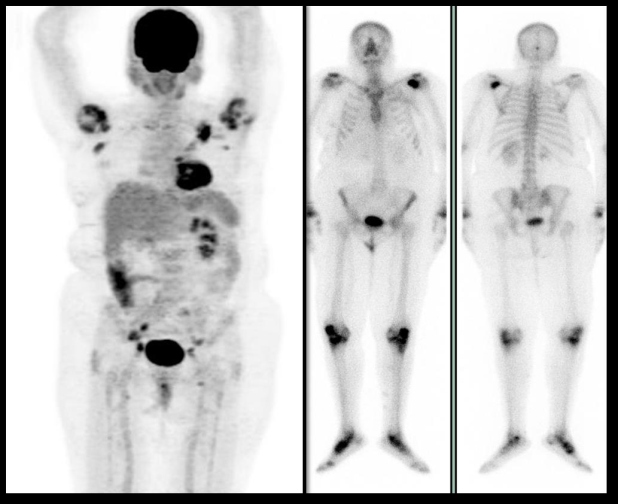

Figura 1.

Figura 1. Paciente de 55 años, con diagnóstico de cáncer de mama ductal infiltrante metastásico de 12 años de evolución. Las diferencias en la resolución y detección de lesiones óseas son notables al comparar la proyección de máxima intensidad del PET-CT (izquierda) con el rastreo óseo (derecha), siendo mucho mayor la sensibilidad para el primer método. De acuerdo a los hallazgos tomográficos, las lesiones óseas encontradas eran mixtas.